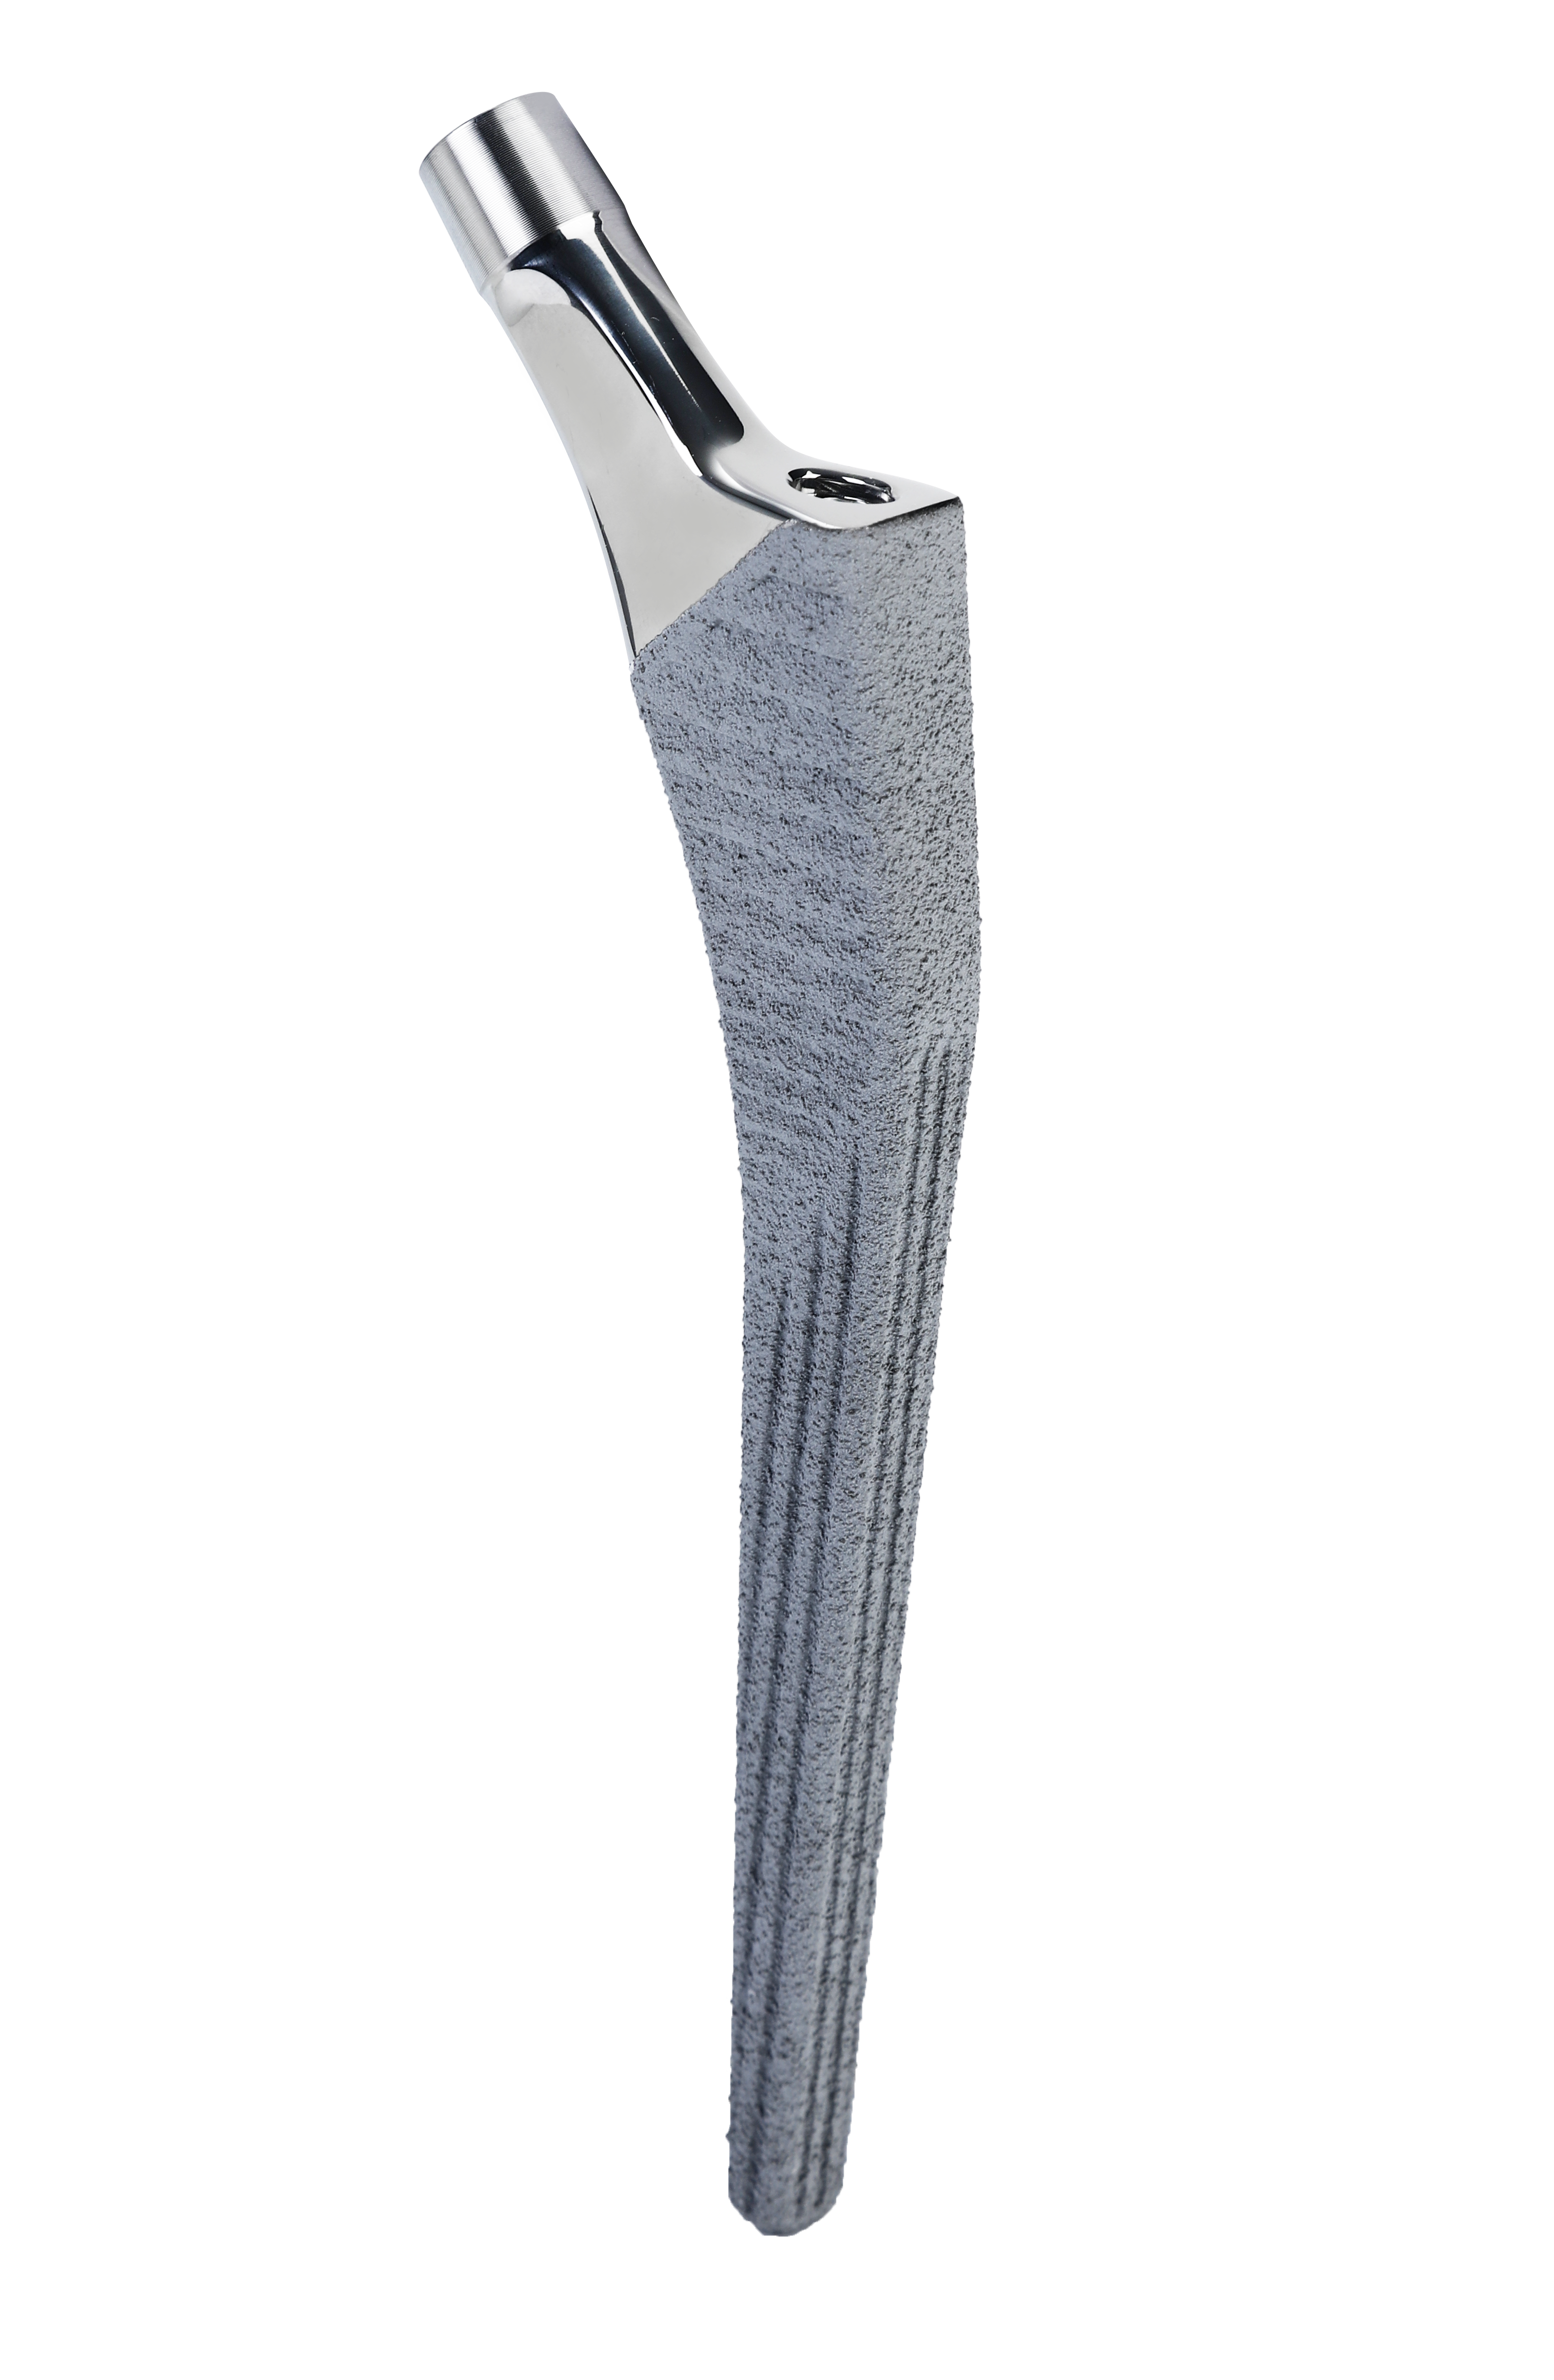

STANDFIRM® BS Femoral Stem

Featuring Ti+HA dual coating, Cementless. As part of the STANDFIRM Hip Replacement System.

-

STANDFIRM® CS Femoral Stem

Featuring Ti (+HA) coating, Cementless. As part of the STANDFIRM Hip Replacement System.